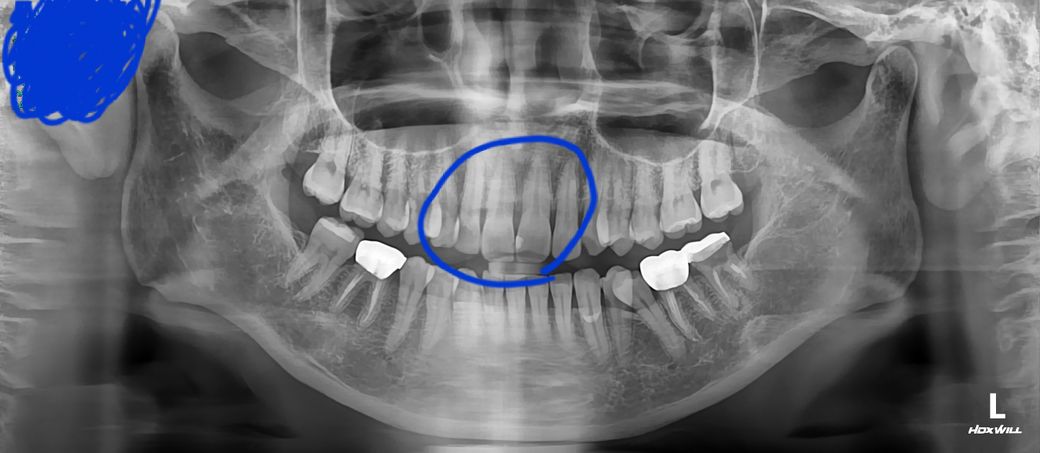

• 4번 째 사진

1. 큰 사진이 파노라마 방사선 사진이고, 작은 사진이 치근단 사진이며 치근단 방사선 사진상(노란색으로 표시하신 사진 기준) 왼쪽이 11번 치아, 오른쪽이 21번 치아 입니다. 만약 두 치아를 동일한 재료로 떼우신 거라면 11번은 기존 재료가 떨어져 나간 상태로 보입니다.

사진으로 봤을 때는 오른쪽 위에 앞니인 11번 치아에 인접면에 충치가 있는 것으로 보입니다.

이전에 메꿨던 재료가 탈락이 되었을 경우에도 해당 부위가 비어 있기 때문에 어둡게 보일 수 있습니다 자세한 확인을 위해서 치과에서 진료를 받아 보세요.